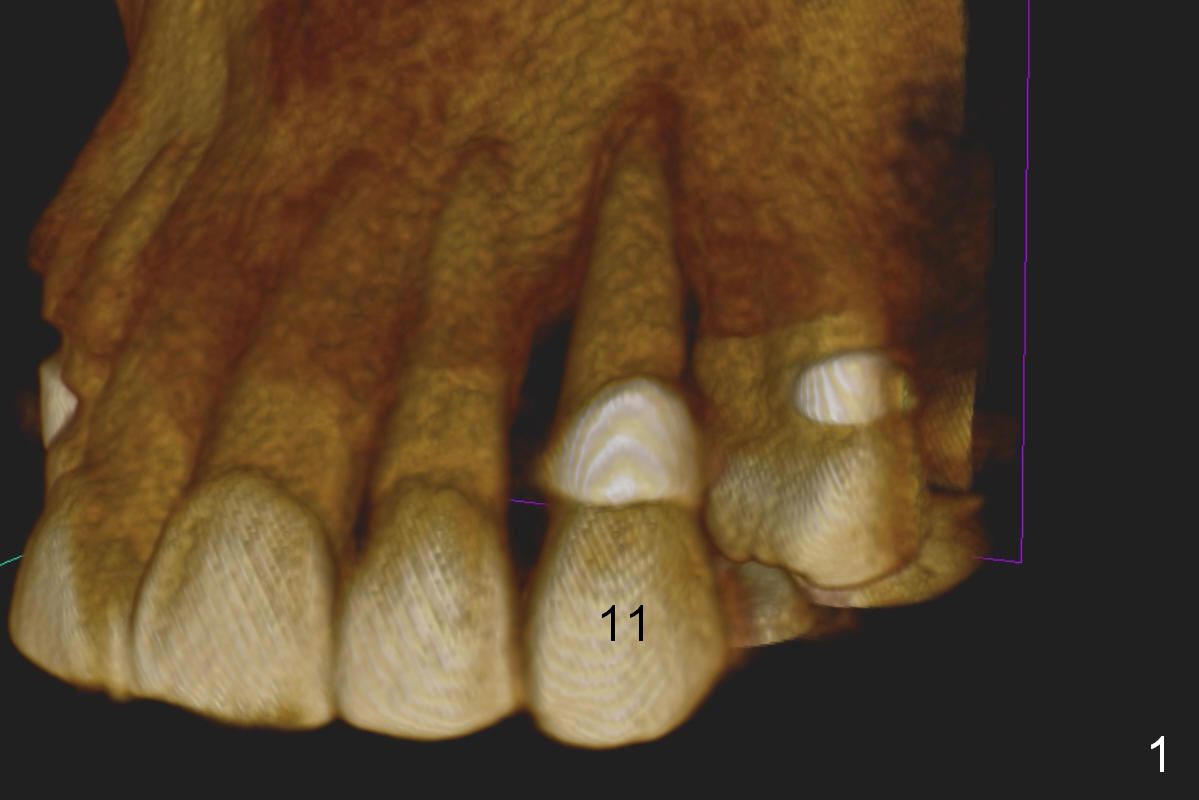

A 65-year-old man has history of Type II diabetes and stroke. He is taking a blood thinner (Xarelto 20 mg qd). The tooth #11 has been mobile for several years. Fig.1 is a CBCT taken 2 years 8 months earlier. The affected tooth has now supraerupted (Fig.2 arrow) with apical abscess (arrowhead).

Bone defect at present should be more severe than CBCT coronal (Fig.3) and axial (Fig.4) sections indicate. After palatal placement of a 5x20 mm tissue level implant (Fig.3 green area) and an appropriate abutment, an immediate provisional is to be fabricated. A block graft is harvested from #12 edentulous region (buccal plate) to the buccal defect at the site of #11 (Fig.4 curved light blue arrow). Prepare surgical handpiece and chisels. The remaining bony defect will be filled with allograft and Osteogen (red circles). The graft site is going to be covered by Osteotape (Fig.3,4 pink curved line), while the donor site is given mixture of allograft and Osteogen and Collagen Dressing. When the soft tissue deficiency is found, connective tissue graft is to be harvested from the palate. If visibility is compromised for these steps, an incision will be made as shown in Fig.5. This should be done with caution considering the medical conditions. Before surgery, ask the patient whether the blood thinner has stopped for a few days or not and how diabetes control is.